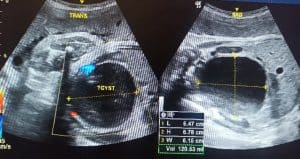

Antenatal radiological assessment: An ultrasound scan done outside our unit, at about 32 weeks of gestation, revealed foetal bilateral hydronephrosis, query a distended foetal urinary bladder with debris, and oligohydramnios. A repeat ultrasound scan done at our unit showed a cystic mass measuring 6.47 x 5.78 x 6.15 cm with a volume of 120 ml arising from the pelvis and containing internal echoes, likely a haemorrhagic ovarian cyst. There was foetal hydroureteronephrosis. Oligohydramnios, with an amniotic fluid Index of 4.49 cm, was also noted. Dilatation of the maternal renal calyces and renal pelvis was found and thought to be physiological changes for pregnancy.

Figure 1: Repeat ultrasound scan showing the foetal pelvic cystic mass with internal echoes